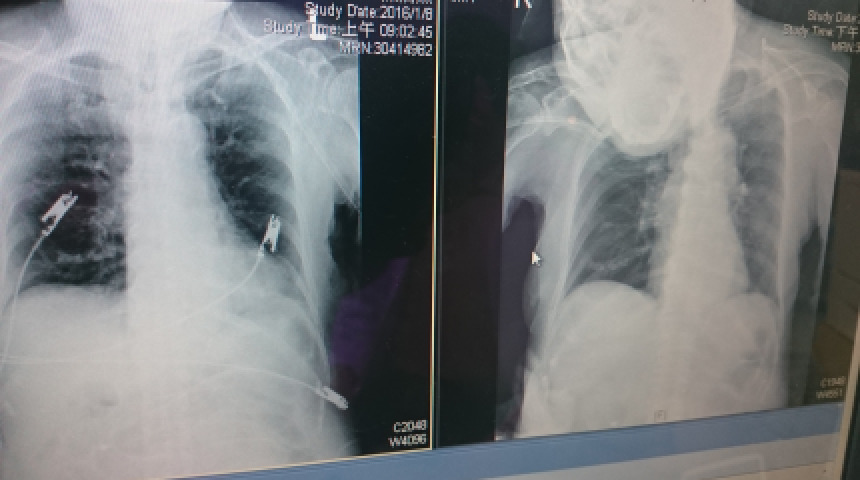

老媽咳嗽不明熱的經驗分享 抗生素針劑的使用 尿管抽換 噴霧器清理 鼻胃管的長度 中醫食物的禁忌

老媽住院與出院後CPR發炎延緩指數的認識 低血鈉的檢討與處置 24穀粉必須持續添加鹽才能符合鈉的需求 體重持續穩定增加